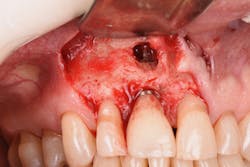

Figure 19: Immediately after incisions and raising a full-thickness flap, suppuration was noted on the apex area of the implant.